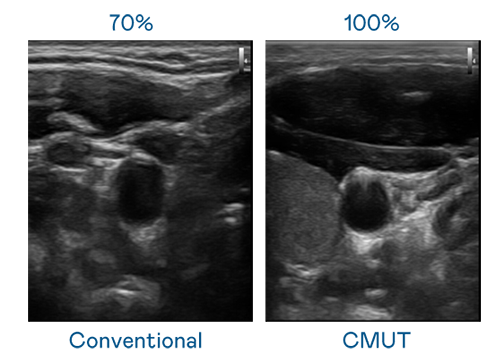

CMUT 技术是一种用电容式微机电元件来产生超音波讯号的技术。与传统 PZT 压电式技术相比,CMUT 频宽增加 30%,更宽频的超音波讯号让影像解析度大幅提升,是实现高影像品质医疗超音波扫描、促进精准医疗发展的关键技术。

大频宽带来超清晰影像

超音波影像的解析度高低,首先取决于探头能发出的讯号频宽。尊龙凯时Ag CMUT 可提供高清晰的超音波讯号,提供高频宽、高灵敏度、影像纹理细节更高的超音波影像,协助医护人员缩短影像判读时间及利用精准的医疗影像进行诊断。